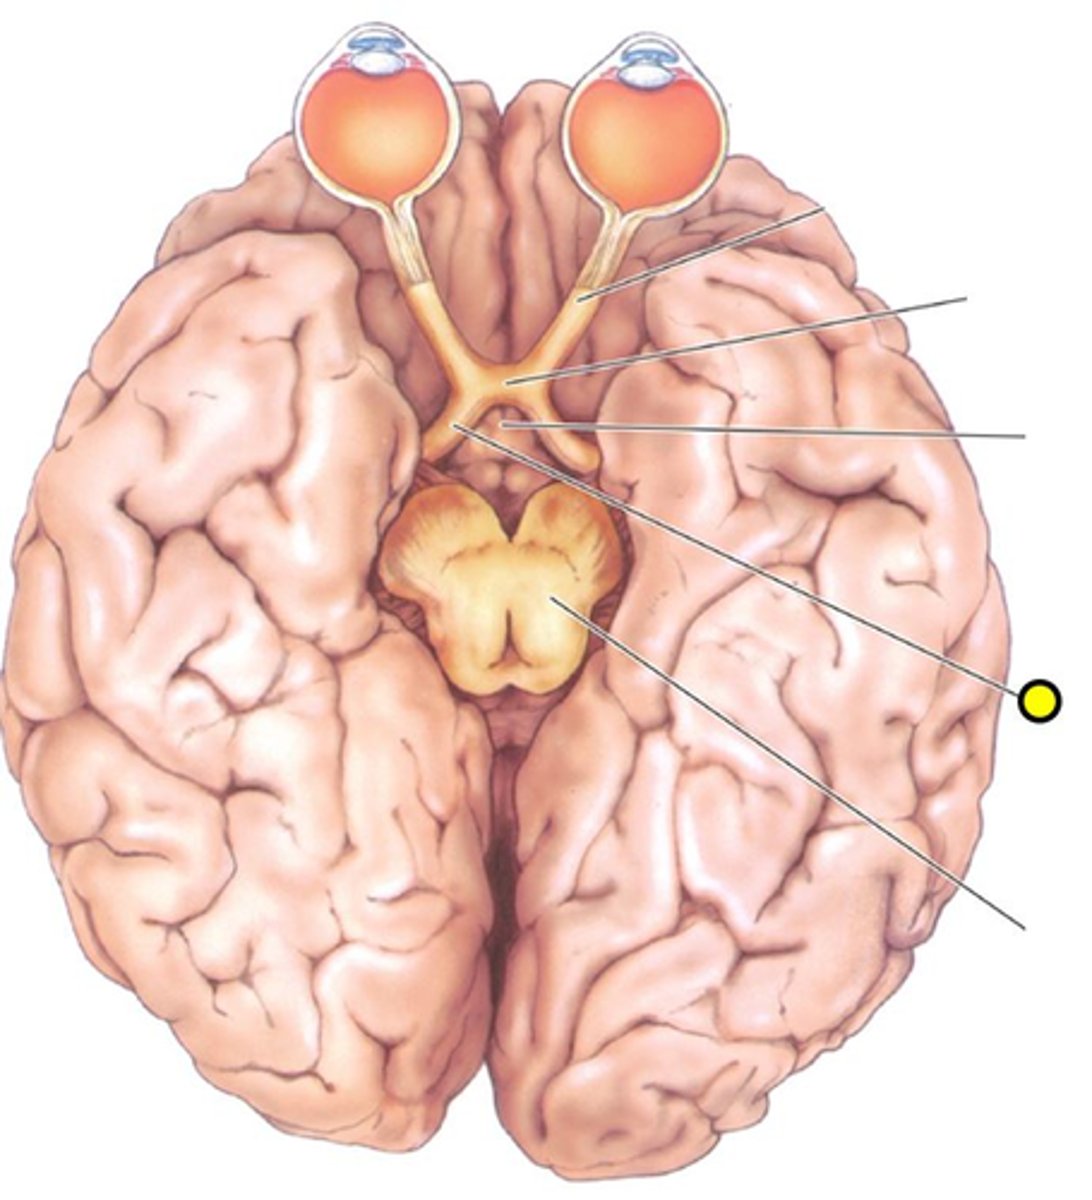

Optic chiasm

point at which optic nerve fibers cross in the brain

Optic nerve

Optic tract

Pituitary gland

Infundibulum

A stalk that attaches the pituitary gland to the hypothalamus.

Olfactory nerve

CN I

olfactory tracts

olfactory bulbs

Optic nerve

CN II

Occulomotor nerve

CN III

Trochlear Nerve

CN IV

Trigeminal Nerve

CN V

Abducens Nerve

CN VI

Facial Nerve

CN VII

Vestibulochochlear Nerve

CN VIII

Glossopharyngeal Nerve

CN IX

Vagus Nerve

CN X

Accessory Nerve

CN XI

Hypoglossal nerve

CN XII